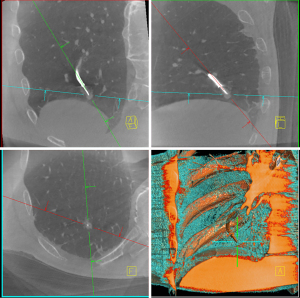

When requested by the proceduralist, the patient was placed in apneic oxygenation. The APL valve was set to 20 cmH2O (25 cmH2O if morbidly obese) with inspiratory pause. The pressure curve was observed to ensure a plateau was reached (Figure 2). The FiO2 was placed at 4 liters per minute (LPM). Apneic oxygenation was performed during portions of the procedure, including navigation, mCBCT spin, catheter adjustments, and biopsy. The use of apneic oxygenation was at the discretion of the proceduralist with no preset patient or lesion specific criteria. Figure 3 details intraprocedural hemodynamic monitoring.

The proceduralist performed intraprocedural imaging to localize the PPL, which potentially included r-EBUS (Olympus Corporation of the Americas), 2D fluoroscopy or mCBCT using the Cios-Spin™ Mobile 3D C-Arm (Siemens Healthineers Inc., Erlangen, Germany). After ensuring proper catheter to lesion positioning via confirmation with intraprocedural imaging, the proceduralist performed the biopsy using a multimodality approach that included transbronchial needle aspiration (TBNA, Flexision needle, Intuitive Surgical) and transbronchial lung biopsy (TBBX, Captura mini biopsy forceps without spike, Cook Medical, Winston-Salem, NC, USA) with possible transbronchial lung cryobiopsy (TBLC, 1.1 mm cryoprobe, Erbe USA, Marietta, GA, USA). Figure 4 shows mCBCT with the tool in lesion. Rapid on-site pathology was available via cytotechnician and cytopathologist for immediate evaluation of samples. Apneic oxygenation was stopped after completion of PPL biopsy. If multiple PPLs were evaluated during the procedure, apneic oxygenation was either continuous or with a period of ventilation per the protocol settings in between PPLs. After the final target PPL, the ventilator was set according to the anesthesia provider’s preference.